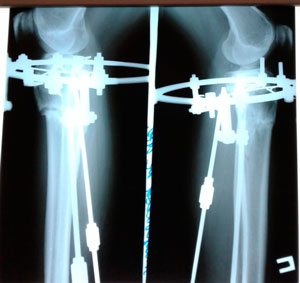

Re: Ровные ножжки!

Сообщение Sekretar Onipko »

Рентген перед фиксацией

Вложения

IMG_2991-06-05-19-05-30.JPG

IMG_2992-06-05-19-05-30.JPG